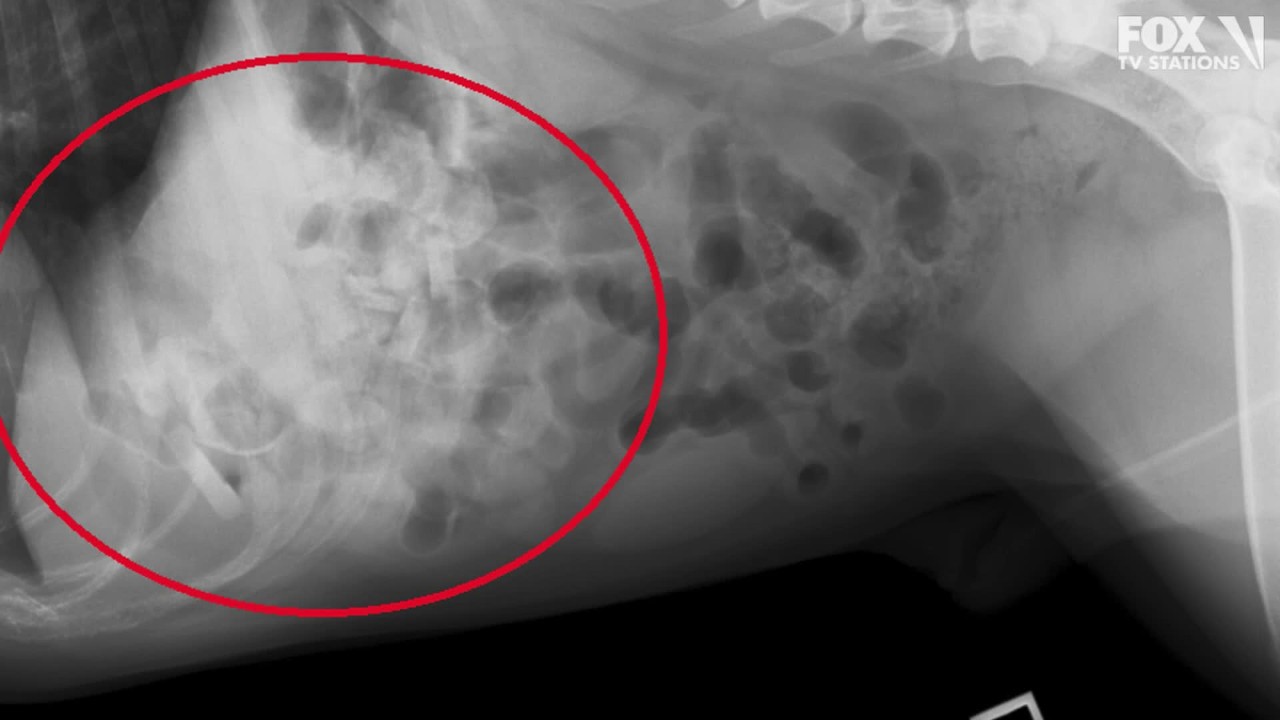

Veterinarians find 19 baby pacifiers in bulldog’s stomach

Vets think the 3-year-old dog, Mortimer, had been taking the pacifiers from the family's two children over the course of months.